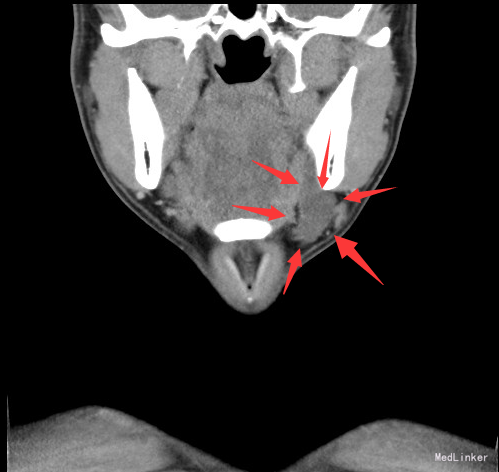

查体:左颌下可触及一肿物,大小约6*3cm,质软,无压痛,与周围组织境界不清。 辅查:颈部螺旋CT:左侧颌下三角区良性囊性肿块,考虑腮裂囊肿可能性大。

诊断:腮裂囊肿 治疗:排除手术禁忌,于全麻下行左颈深部肿物切除+颌下腺及舌下腺切除+颌下淋巴清扫术。术程顺利,术后予以消肿止痛、改善循环、预防感染等治疗,恢复满意。

随访:病理:(颌下及颏下肿物)组织内见一囊肿,囊壁由肉芽组织构成,未见内衬上皮,内含粘液,考虑为粘液囊肿。 讨论:鳃裂囊肿是由胚胎发育中鳃裂残余上皮组织发生的一种先天畸形。胚胎第4周1~4对鳃弓形成,鳃弓之间的腔隙为鳃裂,在胚胎第9周闭 合,如不闭合,残余上皮组织形成鳃裂囊肿。以第二鳃裂囊肿最为常见,约占90%。发生部位依次为耳、腮腺周围;颌下腺外侧、颈动脉间隙外侧、胸锁乳突肌前内侧、上颈后三角区、中、下颈沿胸锁乳突肌前缘,CT表现为沿胸锁乳突肌走行的圆形或类圆形囊性肿块,边界清晰,形态规则。伴有感染时囊壁增厚,边界不清,增强扫描囊壁明显强化。